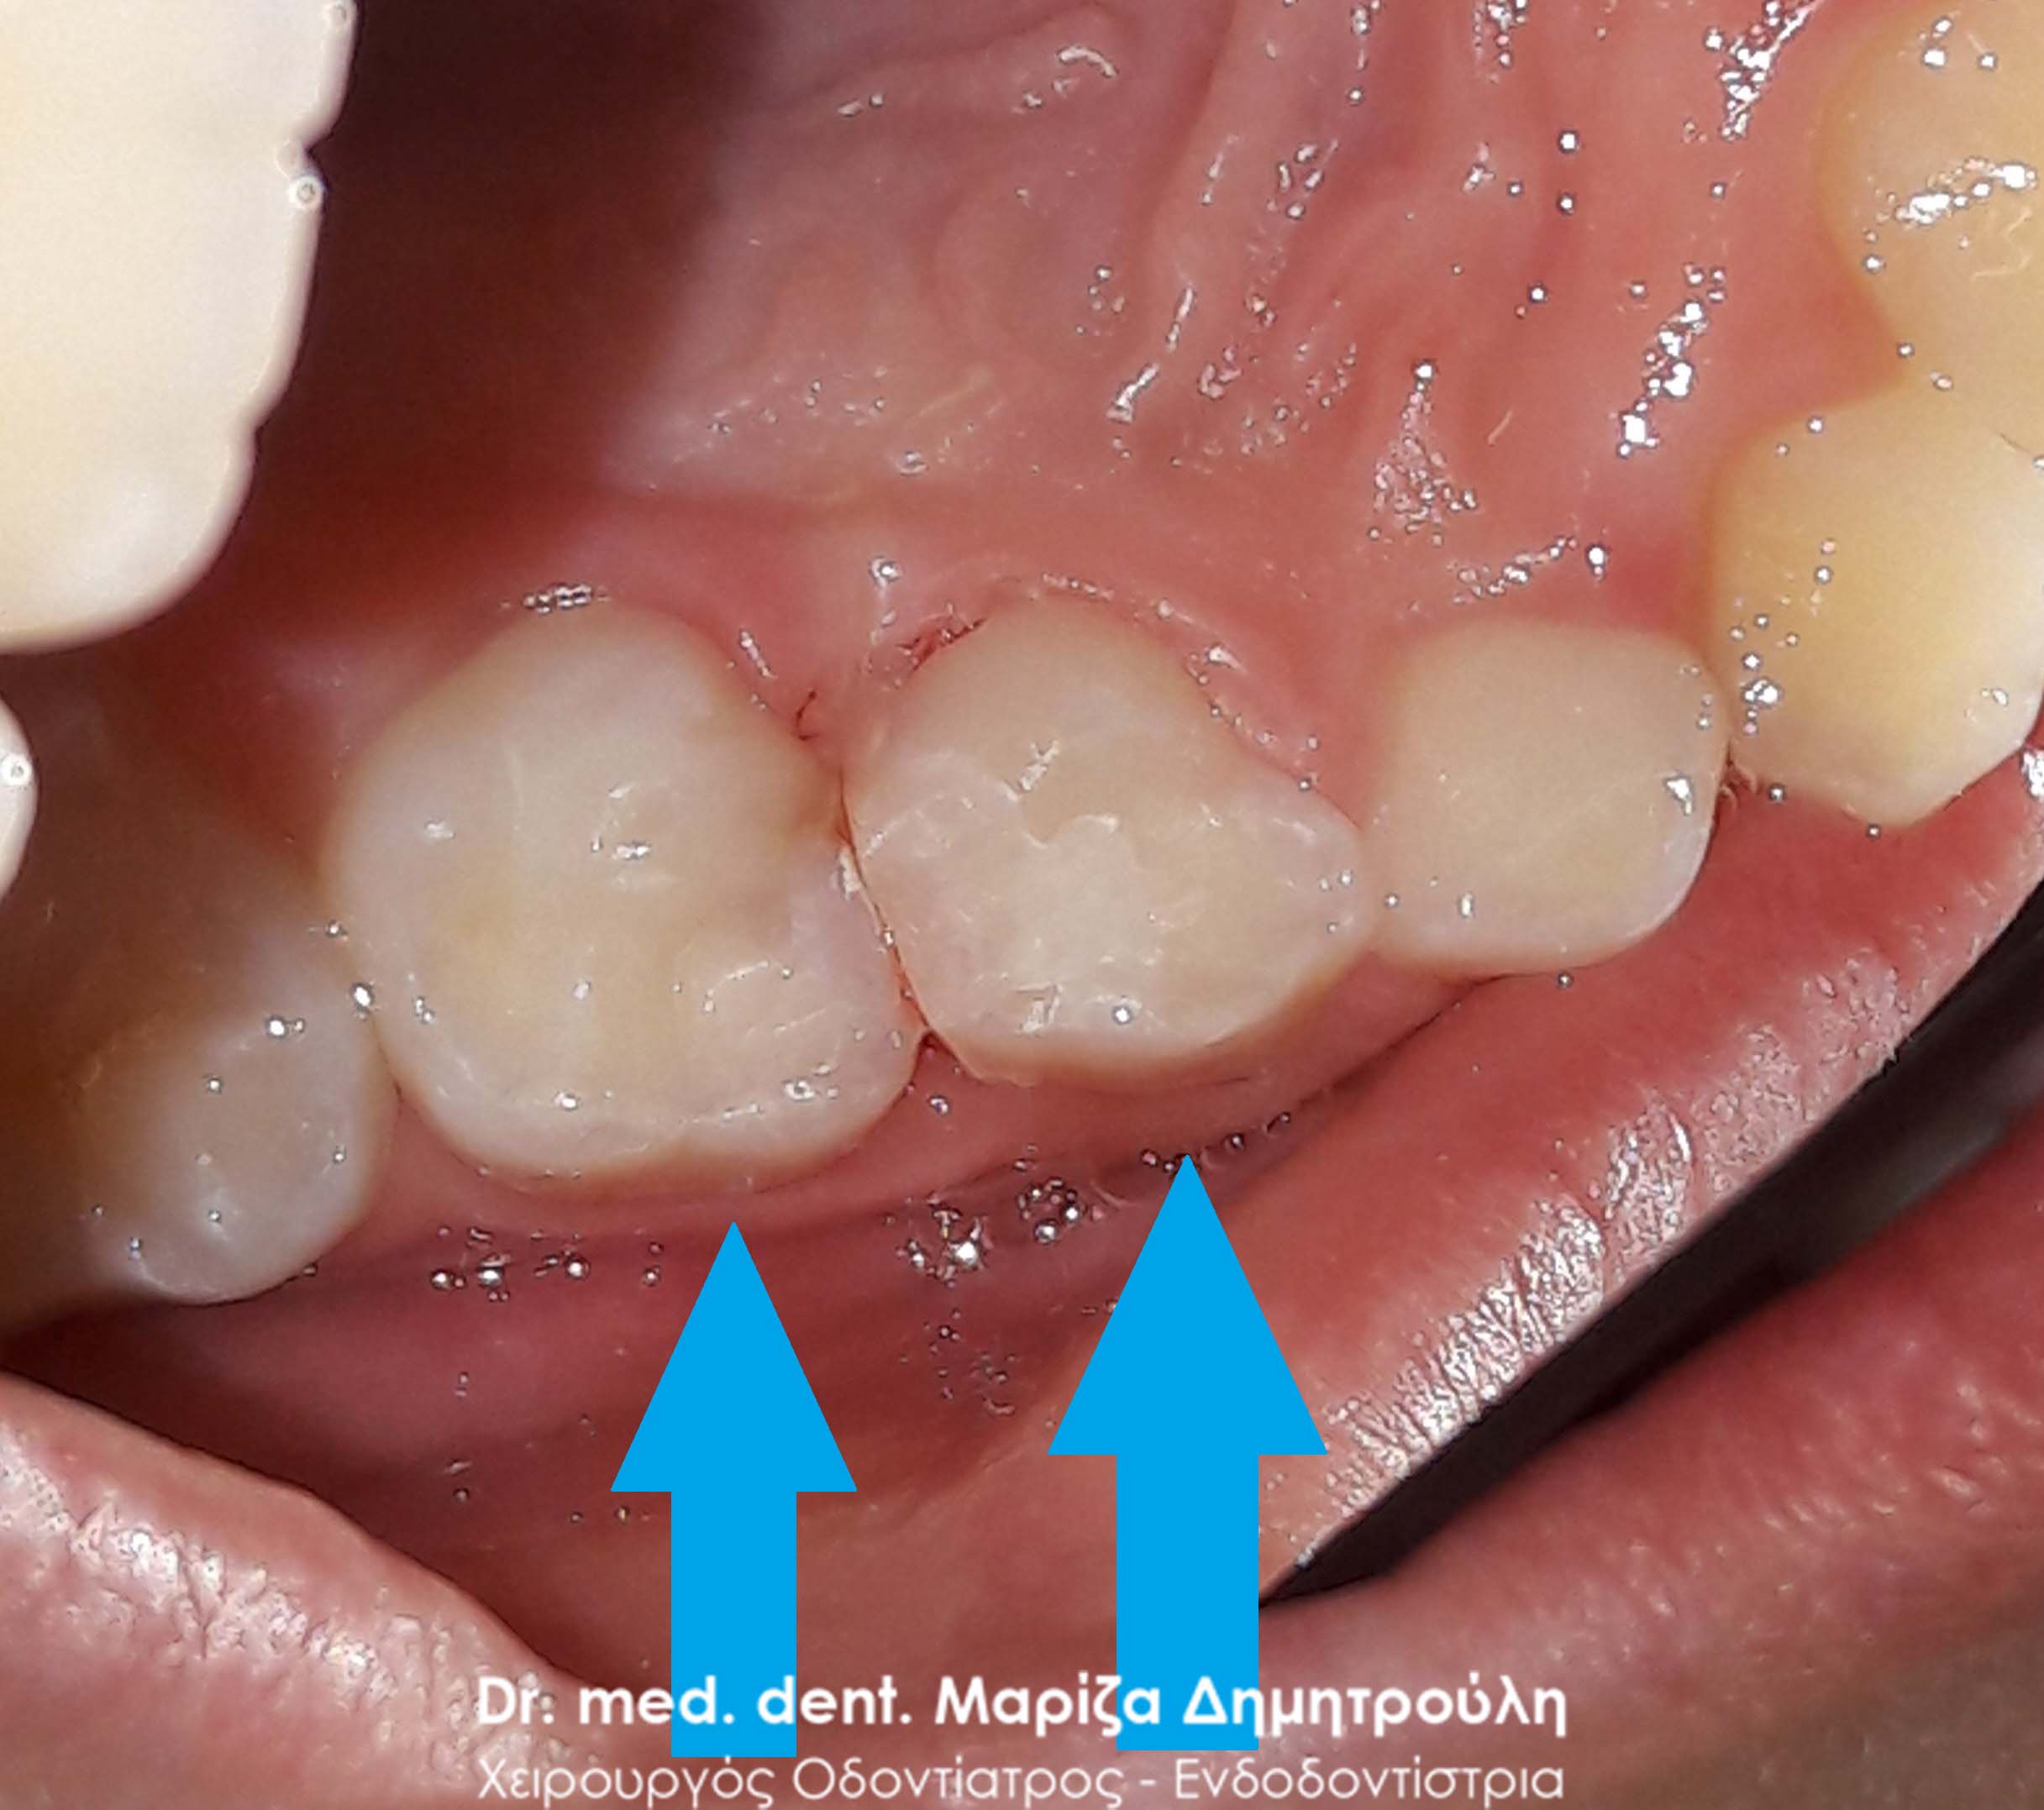

Ο ασθενής παραπονιέται για πόνο κατά τη μάσηση στη δεξιά πλευρά της άνω γνάθου. Η κλινική εξέταση αποκάλυψε δύο μικρές τερηδονικές κοιλότητες, οι οποίες αποκαταστάθηκαν με λευκό σφράγισμα ρητίνης.

ΠΡΙΝ

ΜΕΤΑ